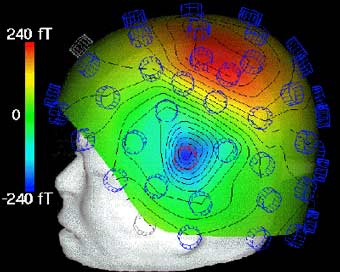

Нужно отметить, что этап наложения электродов остается наиболее трудоемким при проведении ЭЭГ – исследований, он практически не поддается автоматизации и требует участия опытного квалифицированного специалиста. Перспективным направлением решения этих проблемм является метод магнитоэнцефалографии (МЭГ). В нем используются магнитные, а не электрические поля (как при ЭЭГ). МЭГ определяет направление аномальной электрической активности мозга, а не только усиливает сигналы. Многие ученые считают, что МЭГ дополняет ЭЭГ, но его применение в основном пока ограничивается исследовательскими целями [7] (рис.15).

Рис. 15. a) Нейромагнитоэнцефалограф и б) -г) Современные способы представления результатов исследований с помощью ЭВМ (с сайтов http://ntl-cbm.narod.ru/MEG-SITE/index-meg.htm и http://jenameg10.meg.uni-jena.de/gallery.htm)

Согласно современным врачебным стандартам, время, затраченное врачом на анализ и описание результатов в ходе типового ЭЭГ исследования сравнимо со временем, требующимся для регистрации ЭЭГ, включая подготовку пациента, установку электродов, собственно запись и пр. Еще бы, врачу зачастую приходится анализировать одновременные записи нескольких десятков сигналов. Очевидно, что удобство представления информации является одним из важнейших факторов, влияющих на время проведения исследования и правильность интерпретации результатов. Тут неоценимую помощь энцефалографисту предоставляют современные ЭВМ. Например, в программном обеспечении, поставляемым с большинством современных энцефалографов присутствуют средства топографического картирования, в том числе при трехмерной визуализации [1, стр 141]. При таком картировании различными оттенками цвета отображаются амплитудно-частотные свойства сигналов во всех используемых отведениях в любой момент времени непосредственно на схематическом изображеннии головы человека как, например, на рис. 15 б, г.